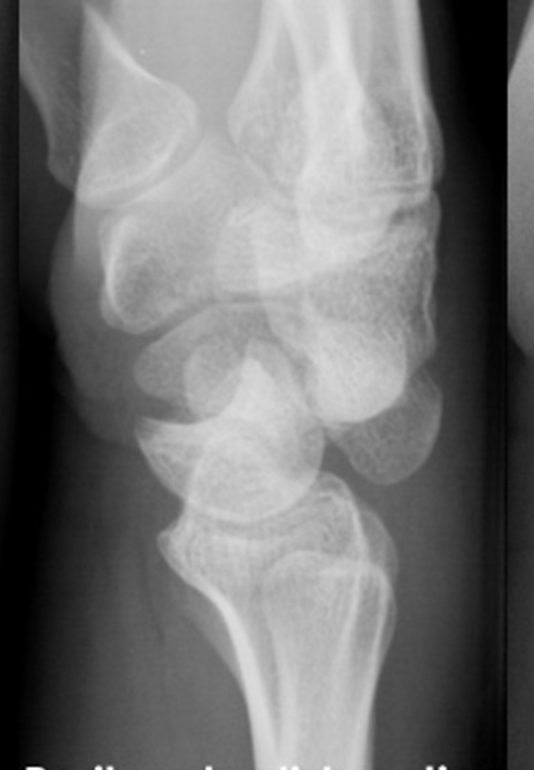

- Scaphoid Fractures: Advanced Clinical Guide to Anatomy, Biomechanics, & Management

- Mastering Carpal Fracture Fixation: An Intraoperative Guide to Non-Scaphoid Injuries